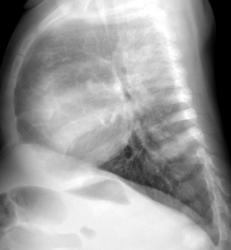

Ребёнок 1год жизни, поступил к нам в клинику с жалобыми, со слов родителей, повышение температуры до 38-39 градусов, не продолжительный мало продуктивный периодический кашель, по анализу крови лейкоцитоз и повышение СОЭ. Напрален к нам предворительным диагнозом: пневмония ? Наши снимочки:

Хотелось бы услышать мнение большинства и есть ли показания для проведение МСКТ-ОГП? В дальнейшем продемострирую более информативную картину.

Я бы расценивал представленную картину, как пневмонию. Показания для КТ? Да, хотелось бы рассмотреть тень более детально, но если течение стабильное, обычное, можно ограничиться динамикой Профессиональный раж хорошо, а как с РБ? Если необоснованно сканировать таких мелких детей, это неизбежно приведет к увеличению онкозаболеваемости.

Да, на рентгенограмме, произведенной в прямой стандартной проекции на фоне сердечной тени визуализируется "шаровидная тень", и довольно существенных размеров. Но где она, такая хорошо дифференцирующаяся на боковой рентгенограмме.

А вот по боковой рентгенограмме меня весьма сильно "смущает" задний сегмент верхнгей доли.

А тело позвонка, отмеченного желтой стрелкой не смущает?

На боковом видно неоднородную инфильтрация, малой интенсивности, если обратите внимание на позвонок, интенсивность его изменена, за счёт наложения инфильтрации:

Врача МСКТ осадили по поводу наличия опухоли или абсцесса, но ни как не пневмонии, а вот и сканы;

Как видно можно было и без МСКТ обойтись, а знал бы я такой подход к ребёнку, написал бы просто сегментарная пневмония.

На мой взгляд, обычная сегментарная пневмония, тем более, в клинику укладывается. Вот сердце немного великовато. Рекомендовала бы УЗИ.